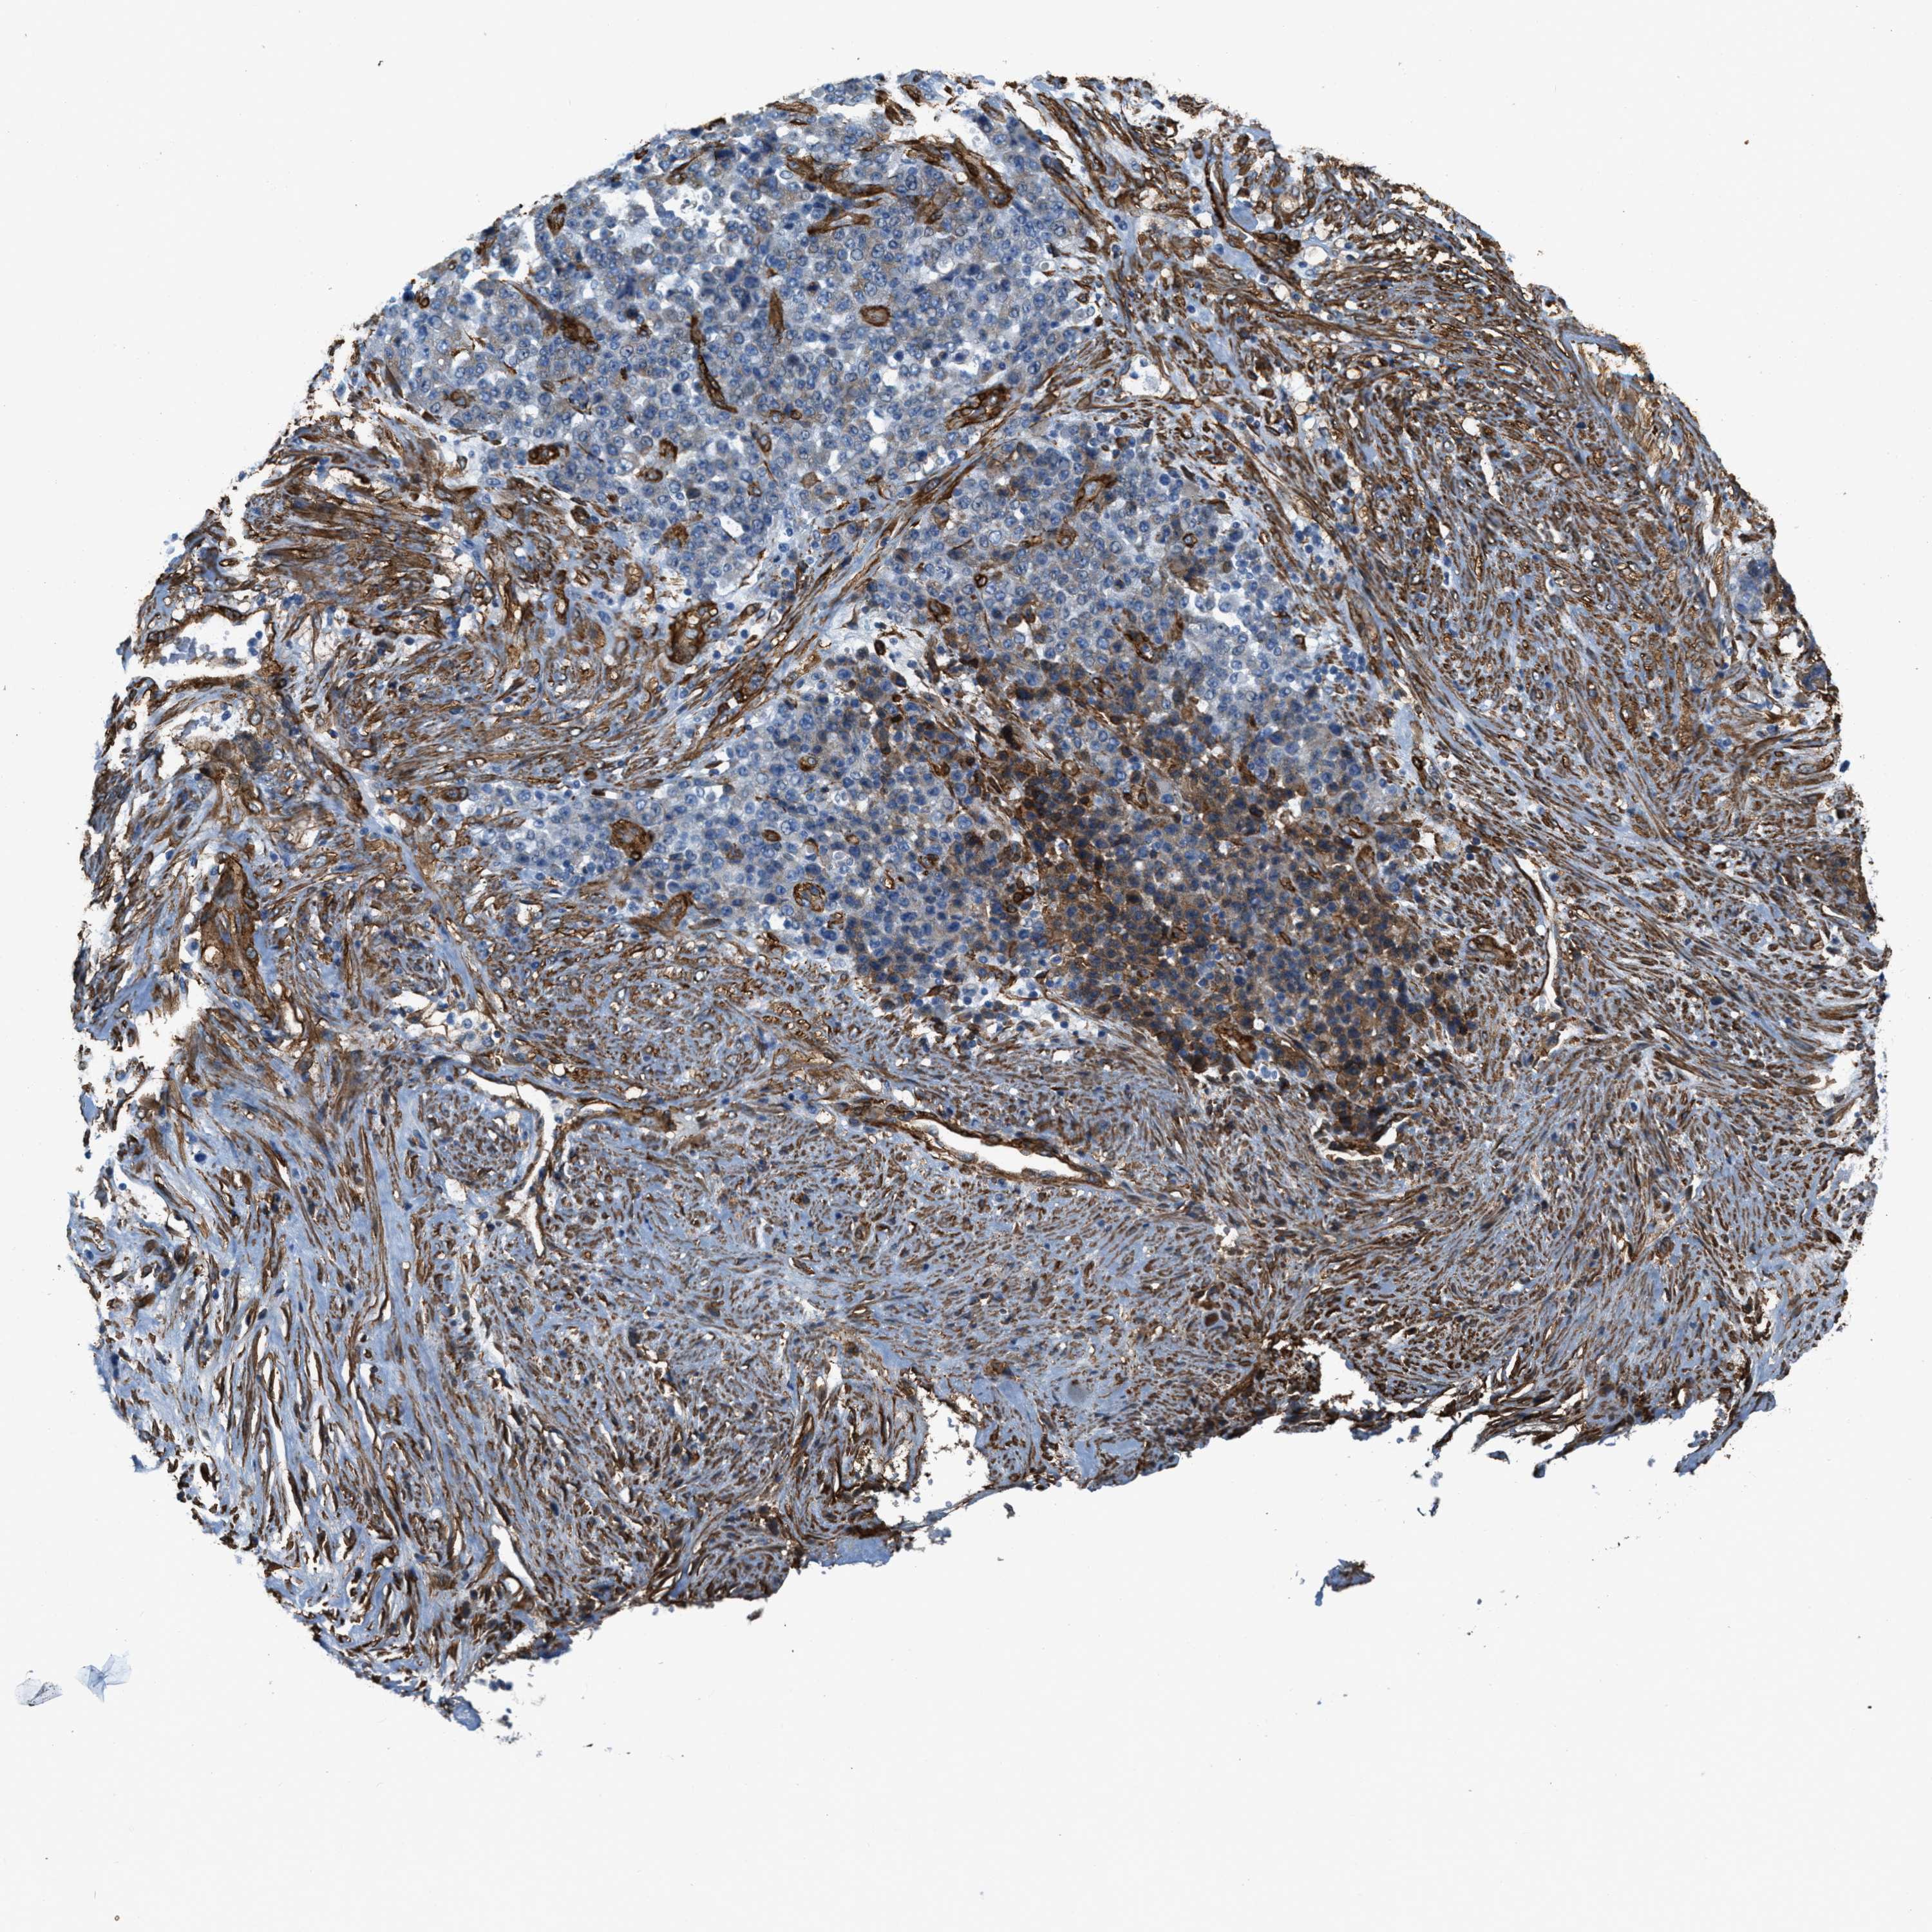

STOMACH CANCER - Protein expressioni

A mouse-over function shows sample information and annotation data. Click on an image to view it in a full screen mode. Samples can be filtered based on level of antibody staining by selecting one or several of the following categories: high, medium, low and not detected. The assay and annotation is described here.

Note that samples used for immunohistochemistry by the Human Protein Atlas do not correspond to samples in the TCGA dataset.

Antibody stainingi

Antibody staining in the annotated cell types in the current human tissue is reported as not detected, low, medium, or high, based on conventional immunohistochemistry profiling in selected tissues. This score is based on the combination of the staining intensity and fraction of stained cells.

Each image is clickable and will lead to virtual microscopy that enables deeper exploration of all samples and also displays staining intensity scores, fraction scores and subcellular localization as well as patient and tissue information for each sample.

Antibody HPA008066

Antibody HPA017330

Antibody CAB000006

Staining

High

Medium

Low

Not detected

Intensity

Strong

Moderate

Weak

Negative

Quantity

>75%

75%-25%

<25%

None

Location

Nuclear

Cytoplasmic/membranous

Cytoplasmic/membranous,nuclear

Adenocarcinoma, NOS